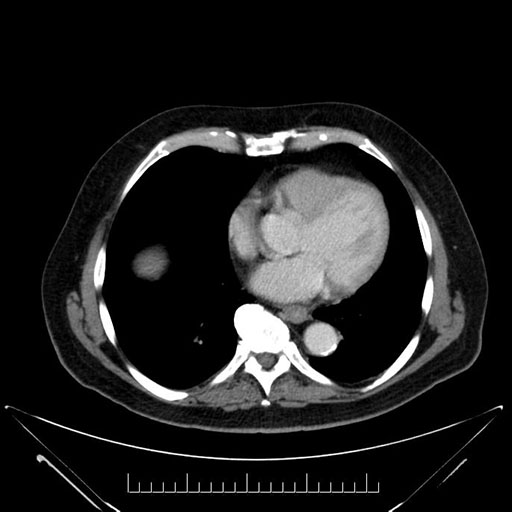

Whipple (pancreaticoduodenectomy) [case 7]

Axial - stented